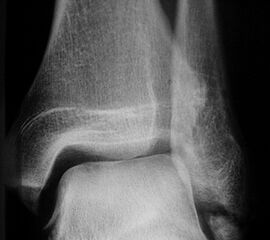

Röntgen

Die Standard Röntgendiagnostik des Sprunggelenks umfasst Bilder in anteriorposterioren (a.p.) und im seitlichen Strahlengang 6. Für die exakte Abbildung des Innenknöchels müssen beide Malleolen parallel zur Röntgenplatte zu liegen kommen. Je nach Torsion der Tibia macht dies eine Innenrotation des Fußes zwischen 10° und 30° erforderlich (Abb. 3).

Os trigonum

Das Os trigonum lässt sich als isolierter Knochen dorsal des Talus seitlichen Röntgenbild darstellen. Normalerweise hat das Os trigonum keine klinische Relevanz. Bei entsprechenden Beschwerden und einer Aktivierung im MRT kann der Knochen arthroskopisch entfernt werden. Gehäuft beobachten wir eine mechanische Problematik durch das Os trigonum bei jugendlichen Fußballspielern und Tänzerinnen.